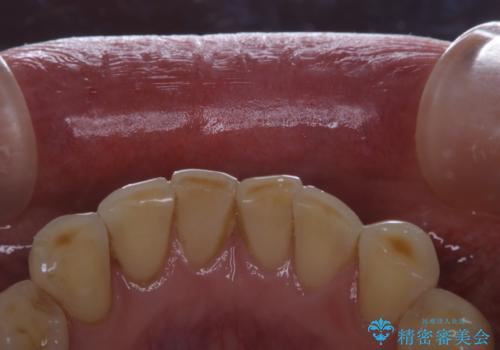

- 前歯のブリッジの治療後も定期的にPMTCを受けている方です。3カ月メンテナンスとのことでPMTC30分コースを行いました。

メンテナンスの際には、治療後のセラミックなどに問題がないかのチェックなどのも行います。